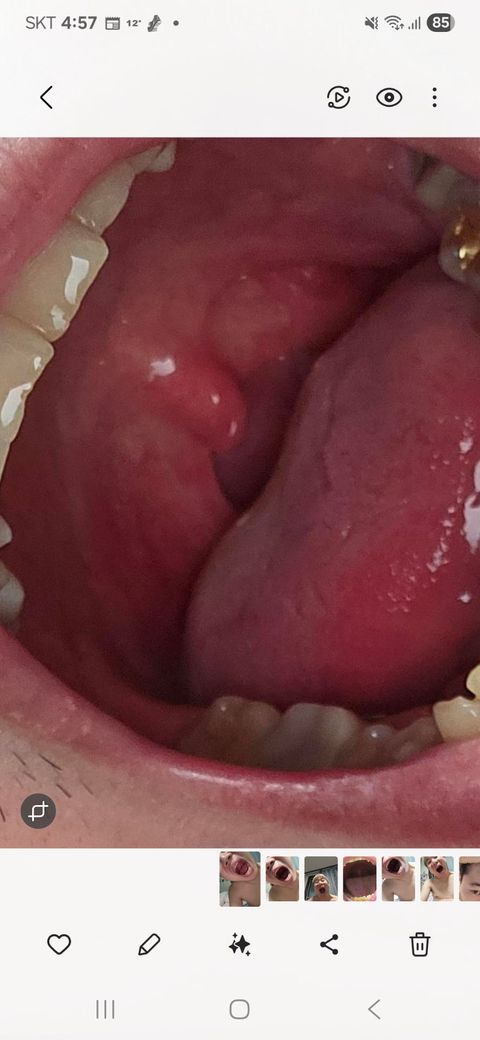

편도가 부었는지 목소리가 잘 나오지를 안는데 편도염 인가요..?

편도가 부었는지 목소리가 잘 나오지를 않는데 편도염 인가요..? 편도염일까봐 불안해요ㅠㅠ 제발 봐주세요

그리고 두통도 심해요

• 편도가 딱히 많이 부어있거나 해보이지는 않습니다. 다만 목 안이 붉게 발적이 있는 것이 인후염 소견은 있어 보입니다. 목소리가 잘 나오지 않는 증상 외에 침 삼킬 때 아프고 따갑고 하다면 인후염을 의심해볼 수 있어 보이는 소견입니다. 보다 구체적이고 자세하게 판단을 받아보시길 희망한다면 이비인후과 진료 및 검진을 받아보시길 권고드립니다.